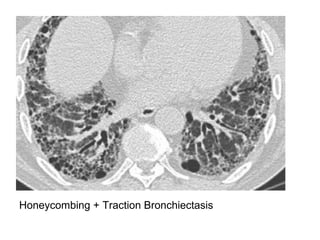

Honeycombing + Traction Bronchiectasis

a) Usual Interstitial Pneumonia (UIP) : Honeycombing

-Also known as Idiopathic pulmonary fibrosis (IPF)

-Apicobasal gradient is even better seen on high-resolution

CT images

-Together with subpleural reticular opacities and

macrocystic honeycombing combined with traction

bronchiectasis, the apicobasal gradient represents a trio

of signs that is highly suggestive of UIP

-Therefore, UIP should be considered in patients who

present with low lung volumes, subpleural reticular

opacities, macrocystic honeycombing, and traction

bronchiectasis, the extent of which increases from the

apex to the bases of the lungs

Honey combing

-Defined by the presence of small cystic spaces

with irregularly thickened walls composed of

fibrous tissue

-Honeycomb cysts often predominate in the

peripheral and subpleural lung regions

regardless of their cause

-Subpleural honeycomb cysts typically occur in

several contiguous layers, this finding can allow

honeycombing to be distinguished from

paraseptal emphysema in which subpleural

cysts usually occur in a single layer

Honeycombing & traction bronchiectasis in UIP

Honeycombing comprises reticular densities caused by the thick walls of the cysts.